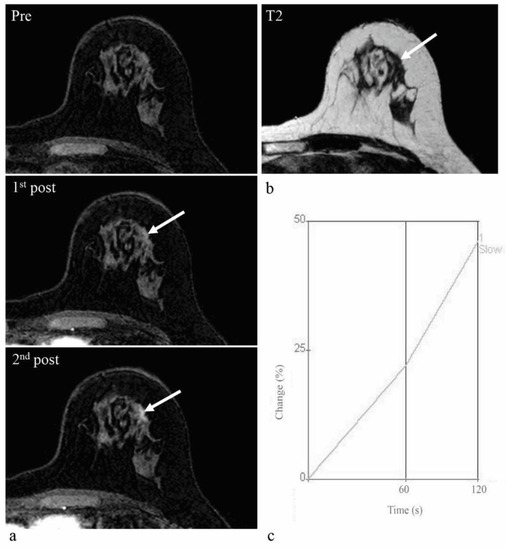

2.4. Kinetic Analysis

| Enhancement rate | <0.001 | ||

| Slow | 24 (16.2) | 0 (0) | |

| Intermediate | 35 (23.7) | 5 (8.5) | |

| Rapid | 89 (60.1) | 54 (91.5) | |

| Enhancement curve type | <0.001 | ||

| Persistent | 100 (67.6) | 18 (30.5) | |

| Plateau | 31 (21.0) | 14 (23.7) | |

| Washout | 17 (11.5) | 27 (45.8) | |